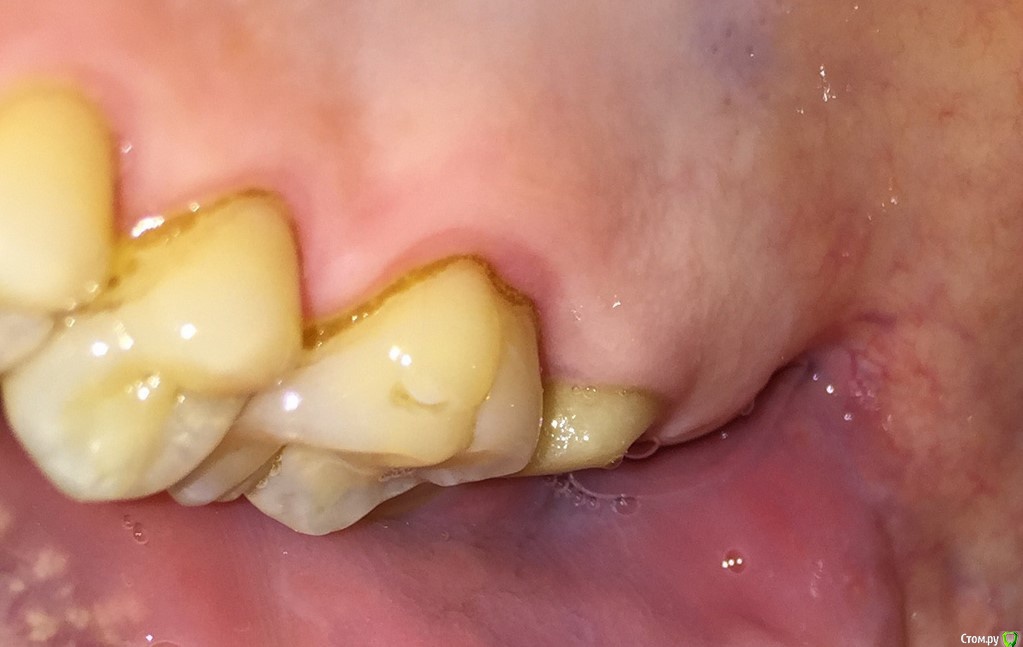

AlexNick Опубликовано 21 сентября, 2017 Поделиться Опубликовано 21 сентября, 2017 Здравствуйте. Меня уже больше года регулярно беспокоят ноющие боли вокруг 6-7 зубов на верхней челюсти (семёрка была давно пролечена резорцин-формалиновым методом, затем установлена коронка). В те дни, когда чувствуется боль, также всегда имеется сильное напряжение жевательных мышц на этой стороне. Год назад делали прицельный снимок - сказали, что всё нормально, только имеется небольшой десневой карман. Но связаны ли с ним боли, точно сказать не смогли. Парадонтолог предлагал сделать кюретаж, если будет "сильнее беспокоить". В последнее время стало беспокоить чаще и сильнее. Я сделал фото (см. ниже) и увидел явное покраснение и припухлость десны. Что это может быть? Парадонтолог у нас принимает только раз в месяц. Ссылка на комментарий